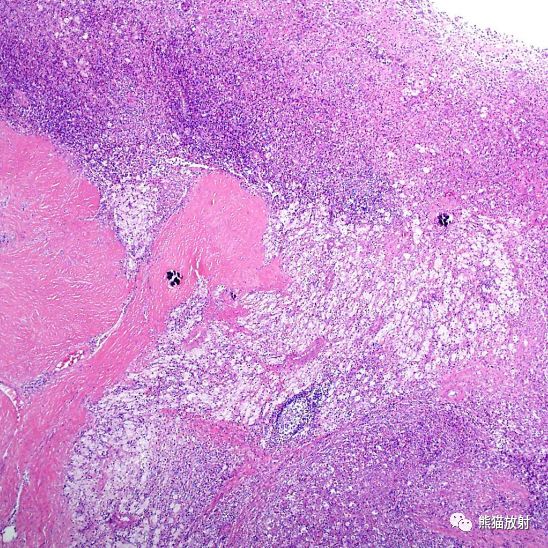

肾脓肿切片

肾脓肿限局性肾组织坏死-炎症-病理学园地

两例疑难术中冰冻病理诊断

清洗标本后,扩张的肾盏和肾盂壁增厚,有多发黄色结节.